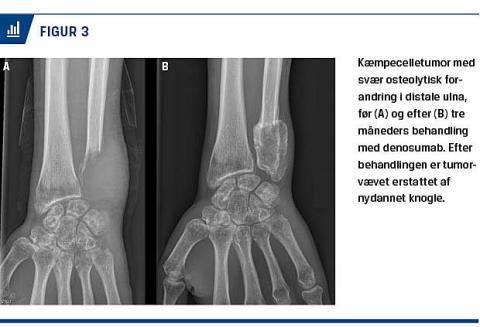

Sørensen et al [19] undersøgte fem patienter og fandt en kraftig og relativt uregelmæssig knoglenydannelse af tumorvævet efter 3-8 måneders Dmab-behandling (Figur 3). Hos tre af patienterne fandt man ved DXA-skanning en 37-44% stigning i BMD i tumorområdet 3-8 måneder efter påbegyndelse af Dmab-behandling.